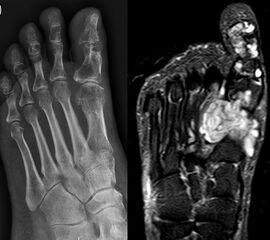

Enchondrom

Das Enchondrom ist der häufigste Knochentumor im Bereich von Hand und Fuß und nach dem Osteochondrom der zweithäufigste gutartige Knochentumor überhaupt. Die geschlechtliche Verteilung ist ausgeglichen, Enchondrome finden sich meist bei Patienten zwischen 20-40 Jahren. Dieser chondrogene Tumor verhält sich meist asymptomatisch, kann aber durch eine Knochenexpansion und Schwellung sowie Spontanfrakturen (Abb. 17) auffallen. Radiologisch zeigen sich in der Regel gut abgrenzbare Osteolysen, Matrixverkalkungen sind typisch aber nicht obligat. Die MRT zeigt typischerweise eine annähernd flüssigkeitsäquivalente Signal­qualität mit niedrigen Signalintensitäten in T1 und hoher Signalgebung in T2, die Binnen­struktur weist eine für chondrogene Tumoren typische Lobulierung mit KM-Aufnahme auf.

Im Gegensatz zu Osteochondromen ist die Lage von Enchondromen nicht auf die Metaphyse beschränkt. Sie finden sich auch im Bereich der Epi- und Diaphysen. Die kurzen tubulären Knochen der Metatarsalia und Phalangen sind bevorzugt betroffen. Hier findet sich die Läsion typischerweise im Bereich der proximalen Phalangen oder distalen Metatarsalia, eine Ausbreitung auf die gesamte Diaphyse ist von hier aus jedoch nicht ungewöhnlich. Die Möglichkeit einer malignen Entartung (Chondrosarkom) ist im Bereich der Metatarsalia und Phalangen im Vergleich zu den langen Röhrenknochen und platten Knochen extrem selten 33. Die übliche Therapie besteht in einer gründlichen Curettage. Je nach Größe des Defekts und Schwächung der Kortikalis kann die Transplantation eines stabilisierenden kortiko­spongiösen Spans notwendig werden. Zusätzliche osteosynthetische Verfahren sind nur selten erforderlich.